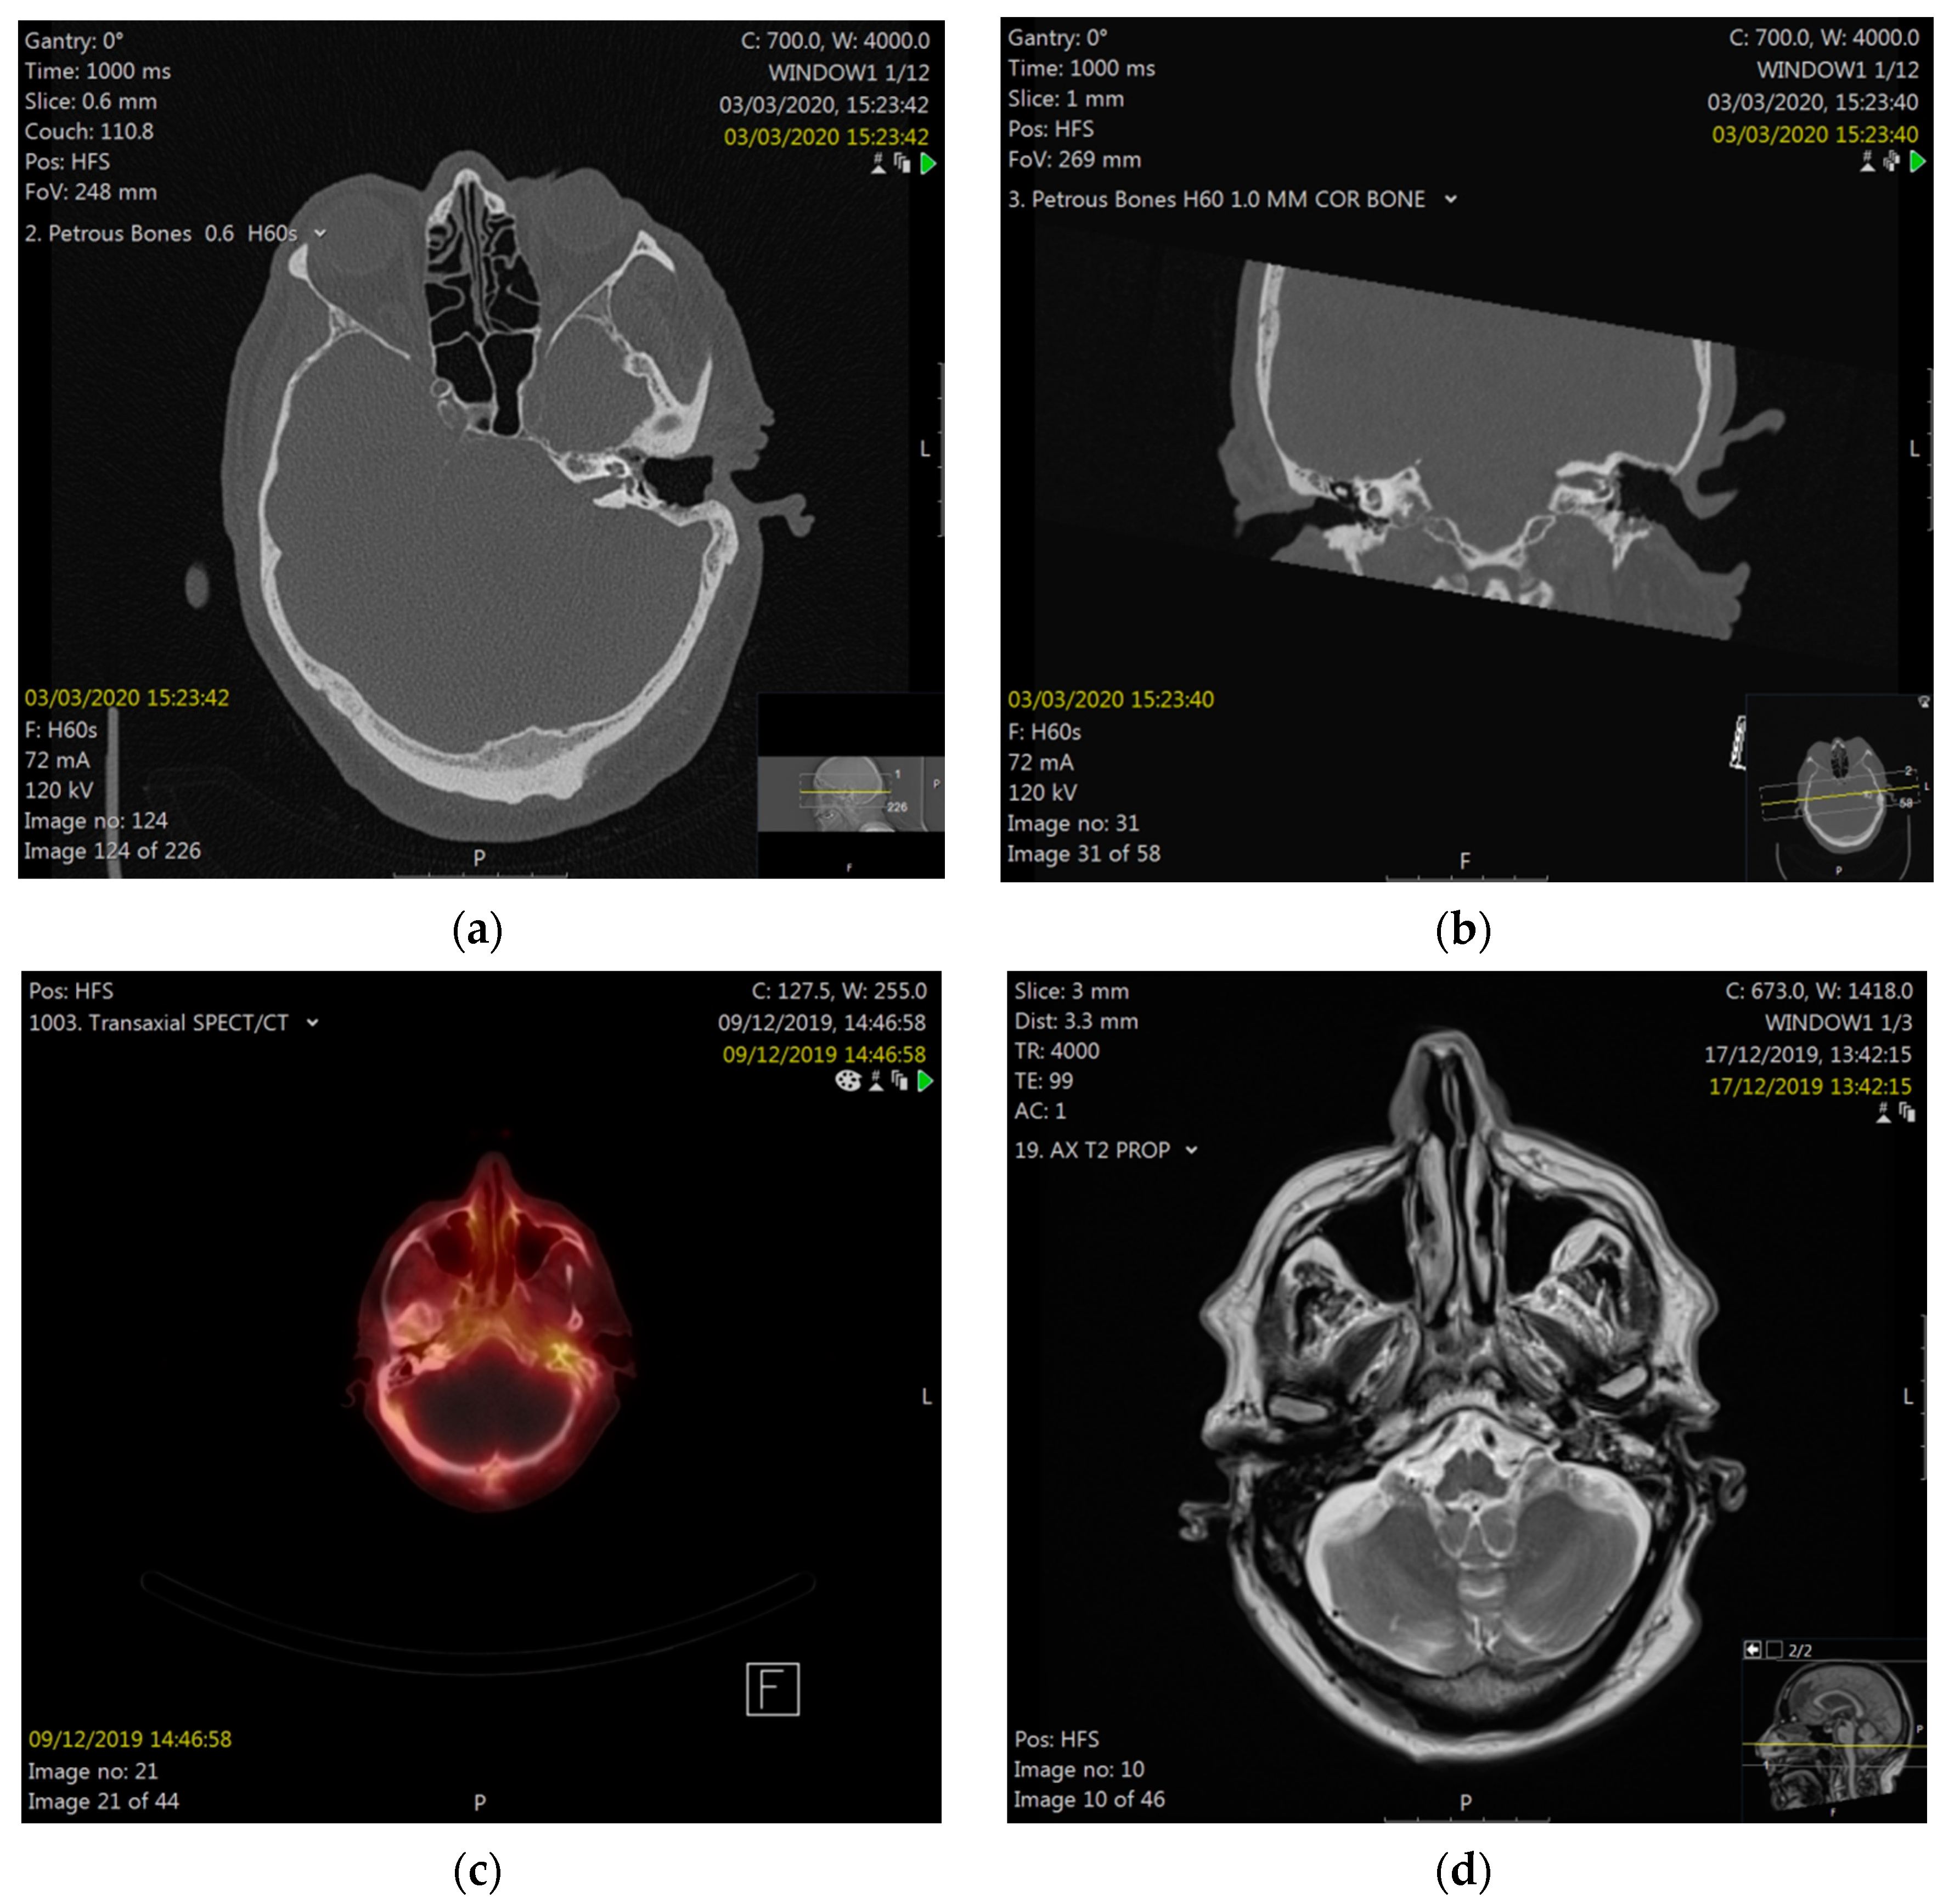

His medical history revealed a left canal wall-down (CWD) mastoidectomy about thirty years ago. Subsequently, twenty years later (ten years ago), a left-sided squamous cell carcinoma of his tonsil was diagnosed, staged T3N1M0 (7th Edition of the AJCC TNM staging system). He underwent curativeinduction chemotherapy, including fluorouracil, docetaxel, and cisplatin, followed by a radiation dose of 66 Gray (Gy) to his left oropharynx and neck, with concurrent cisplatin (Figure 2). Seven years after his tonsil cancer, he had complained of intermittent otalgia and discomfort in his left periauricular, and was treated with microsuction and topical antibiotics for suspected mastoid cavity infections. Further review of his medical history revealed type II diabetes mellitus, which was medicated orally with diabetic retinopathy and peripheral neuropathy.

Figure 2. Upper radiation fields with 66 Gray (Gy) in 33 fractions to the left oropharynx tumor and neck. Radiotherapy was planned with 3D conformal radiotherapy, utilizing two fields to the upper volume: left anterior oblique (LAO) (a) and right anterior oblique (RAO) (b) fields, and the beam’s eye radiographs shown. These fields have been reconstructed on axial CT, to indicate the approximate volume (c). The area where the fields overlap (blue) received 66 Gy.